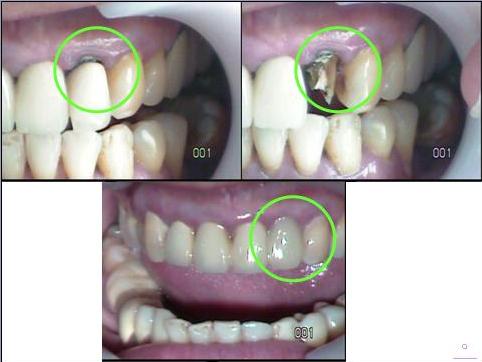

療程實例-3D齒雕

一.不良金屬牙套引起氧化(以3D齒雕

牙套

完美修復)